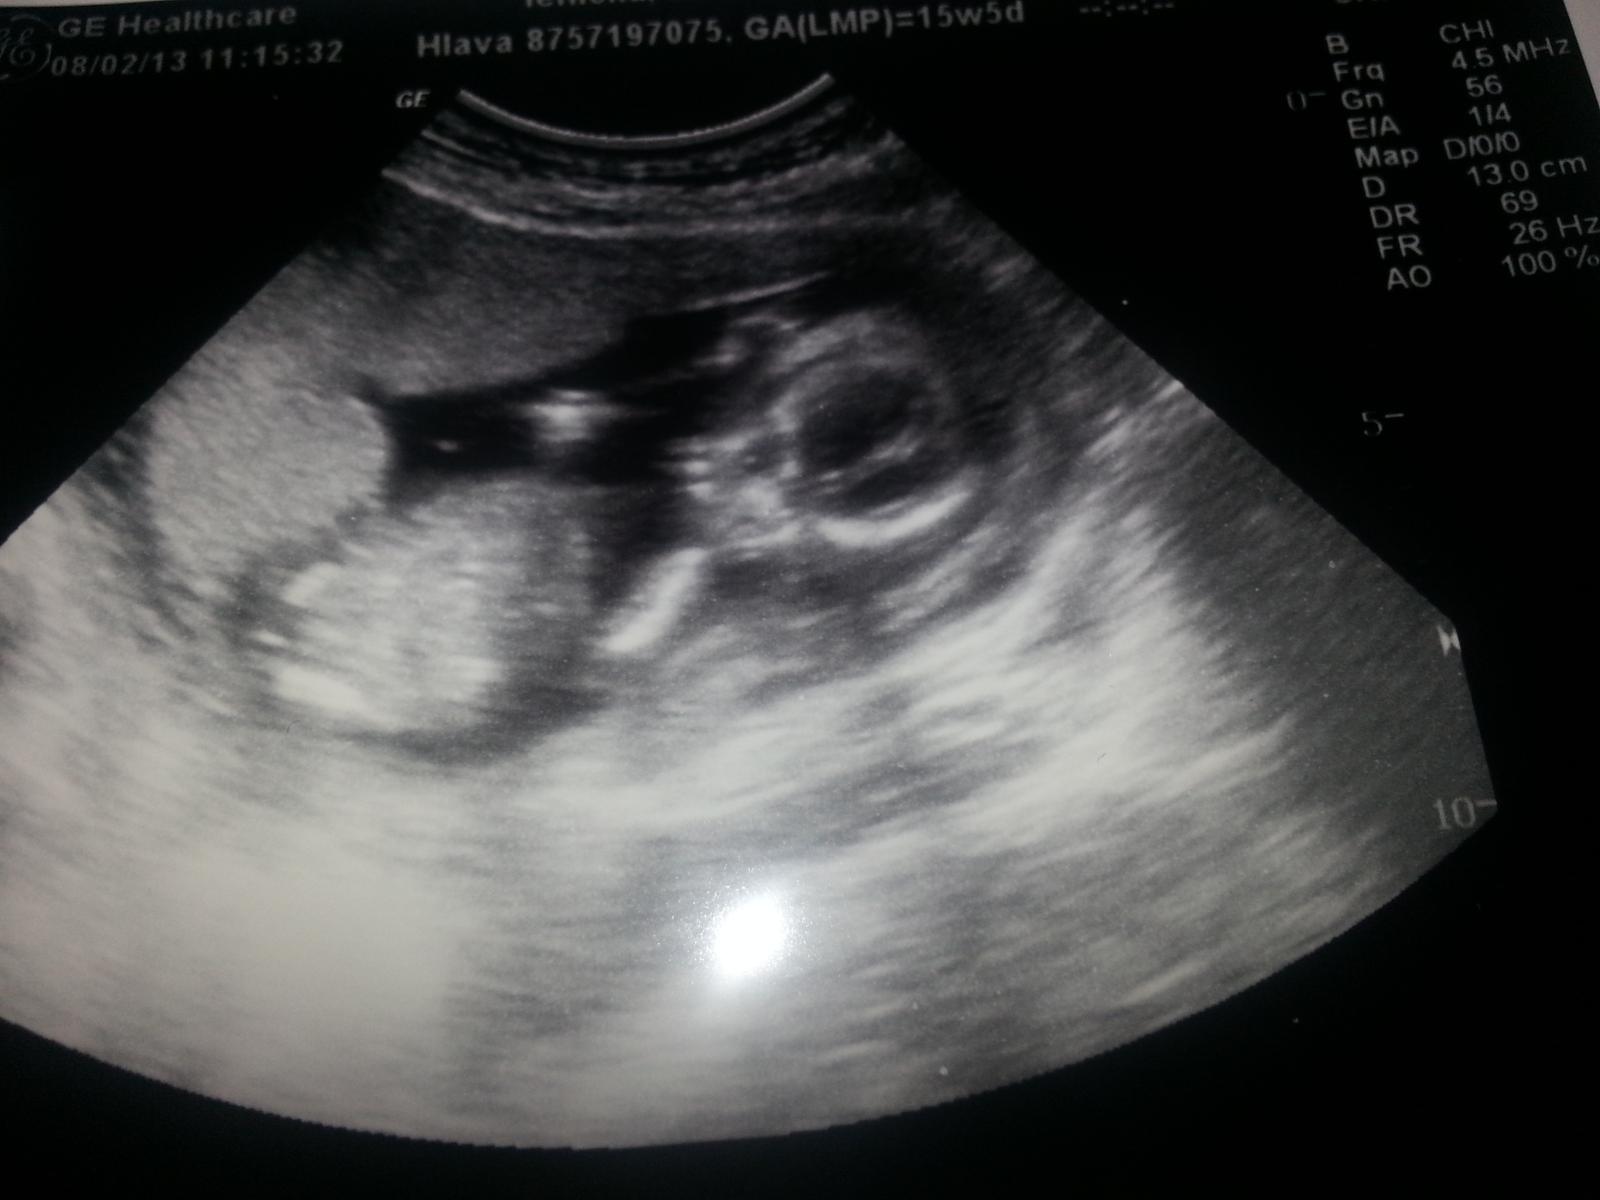

hehe, je tam asi dieťatko 😀 ja teda fakt nič nevidím, bola som teraz na sone, lekár- že chlapec, ja som brmbolček nevidela, ale verím mu. Vždy som obdivovala, čo to tam všetko dokážu nájsť, na tej fľakatej snímke. Ale nech je zdravé, je jedno, čo to je , nie?